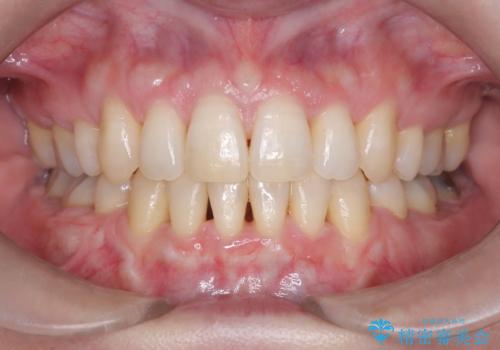

前歯が前に出ていることや歯並びの凸凹が気になるという主訴でした。十分なスペースを確保するため上下左右の第一小臼歯(4番)を抜歯し、そこに前歯を移動させて整列を行いました。矯正装置には目立ちにくい透明なブラケットを選択し、見た目のストレスを軽減。矯正期間中は定期的な通院でワイヤーを微調整し、無理なく確実に歯を動かしました。治療後は前歯が自然な位置に下がり、口元の突出感が解消されるとともに、美しく整った口元に仕上がり、患者様にも大変喜んでいただけました。